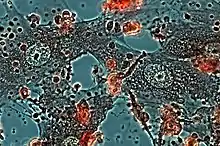

Epithelioid cells formed in culture of mouse peritoneal cells, stimulated by inactivated Mycobacterium tuberculosis, in a micro-chamber for lifetime observation; 14 days of cultivating. Numerous secretory granules are visible in the cytoplasm of cells. In the culture medium epithelioid cell granules and apoptotic bodies from macrophage are visible. Dystrophic altered macrophages are colored red. A method of interferential contrast in polarized light.